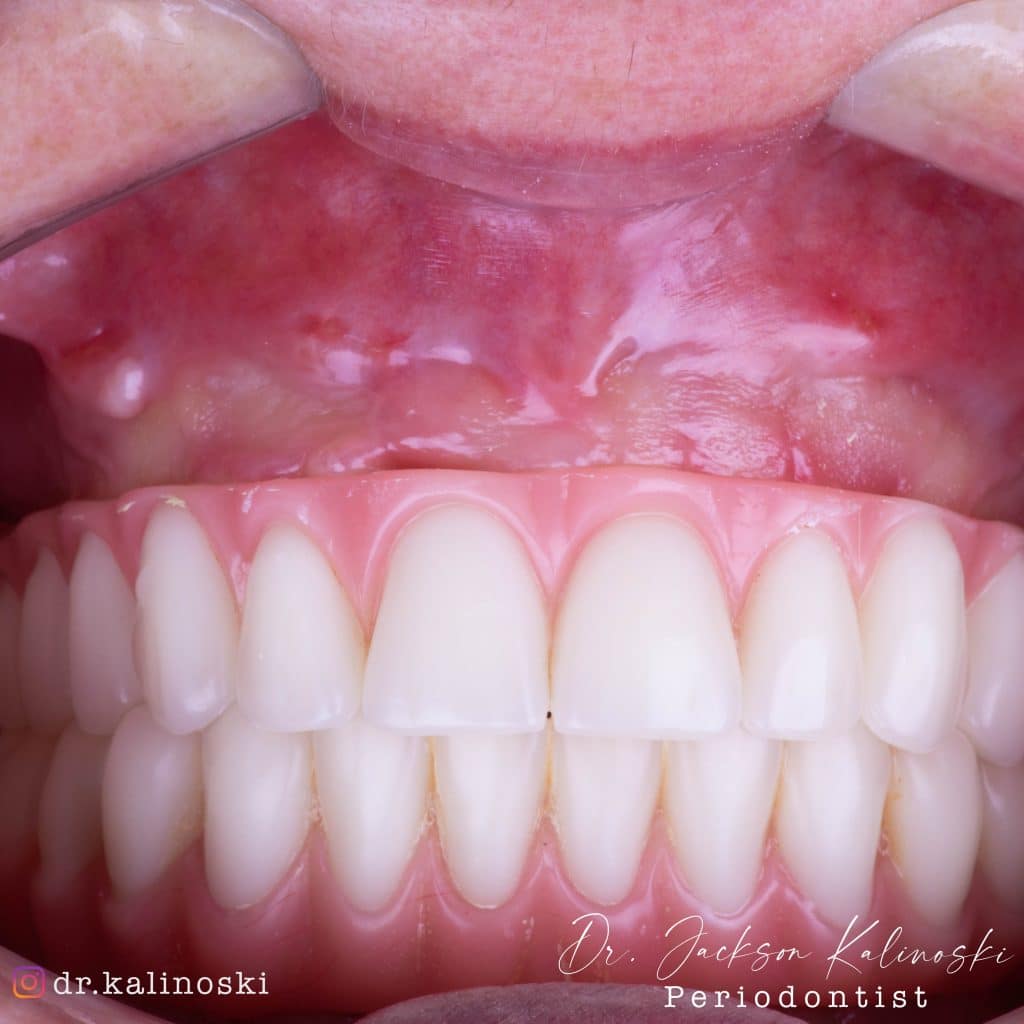

Após 6 meses de maturação óssea e implantes instalados com torque médio de 35 N / cm2.